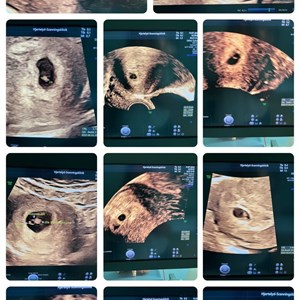

Dagen i dag var de tidlige scanningers dag❣️Fra uge 5 til til uge 11 har vi kigget på en ...